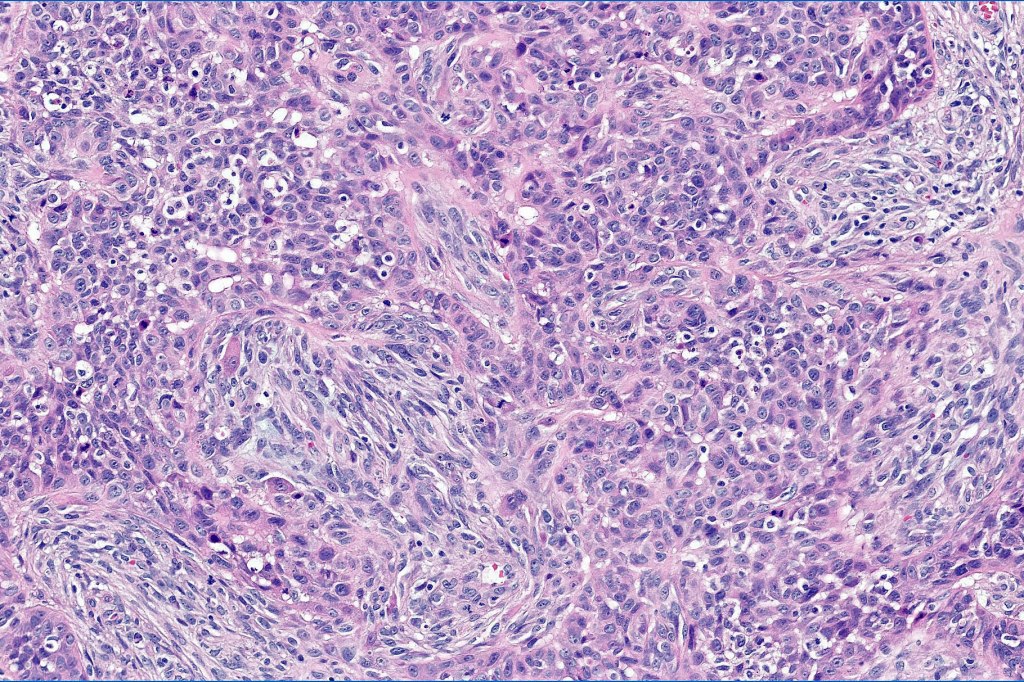

•High grade trichoblastic carcinoma is characterized by high grade carcinoma arising in a trichoblastoma. TP53 &PIK3CA mutations have been documented

•Trichoblastic sarcoma is characterized by readily recognizable trichoblastoma associated with a high grade sarcomatous element